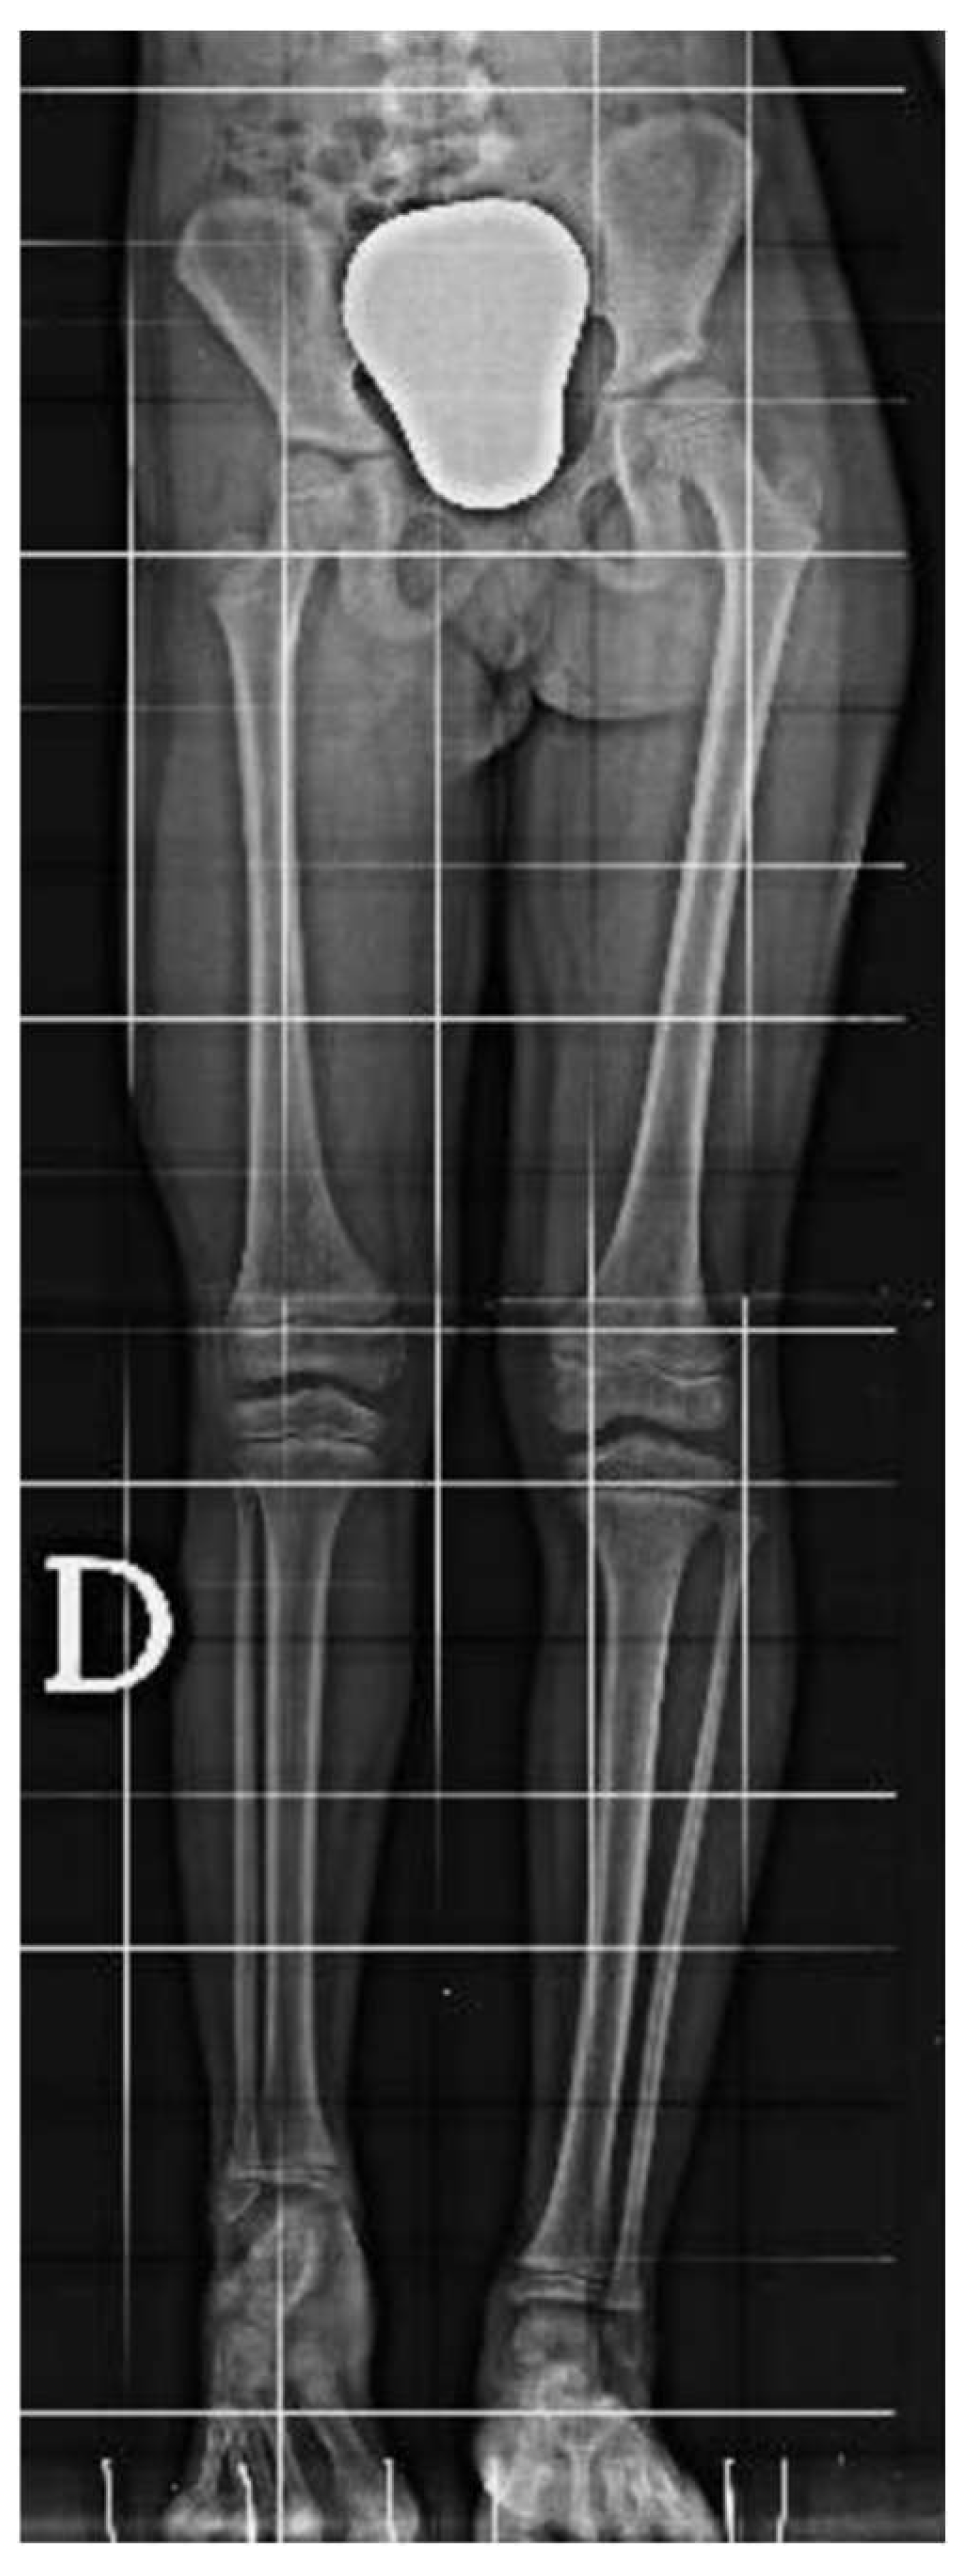

An 8-year-old girl presented to a different hospital with a complaint of leg length discrepancy, right shorter than left. She was brought to local medical attention and promptly diagnosed with congenital femoral deficiency and ipsilateral tibial hypoplasia. At this time, the patient had an acquired leg length discrepancy of 75 mm (femoral 50 mm and tibial 25mm) (Figure 1), she therefore underwent a proximal femoral osteotomy and placement of a LRSTM Orthofix monolateral external fixator to the femur at a different hospital. The procedure was well tolerated with no complications and adequate surgical wound healing. Seven days post-operatively she began the lengthening procedure which consisted of 1/4 turn 4 times per day for a total of 1 mm per day. The patient was followed every two weeks for the first month and then monthly with physical examination and plain film radiographs.

The patient was instructed to start physical therapy for hip and knee range of motion immediately after surgery, while progressive weight-bearing was commenced on the last day of lengthening. At 12 weeks the lengthening goal, 60 mm, was achieved. At 5-months follow up, lower-limb weight-bearing plain radiographs demonstrated that the right femur was within 5 mm of length of the left femur and bone regeneration was visible in the osteotomy gap, however, the study was limited by the inability to fully extend the right knee (Figure 2). Lateral projection radiographs of the right knee showed posterior subluxation of the tibia with respect to the femoral condyles (Figure 3). No action was taken at the time.

At the age of 11, due to the persistent right femoral deficiency, the patient underwent temporary distal femur epiphysiodesis of the left lower limb thus allowing the length of the two femurs to be evened out in just over 2 years. Finally at the age of 14, due to the residual tibial hypoplasia (≅ 40 mm) and valgus knee (Figure 6), she underwent a proximal right tibial osteotomy and placement of an antegrade PRECICE® expandable intramedullary nail and temporary femoral distal medial emiepiphysiodesis (Figure 7) (Figure 8).